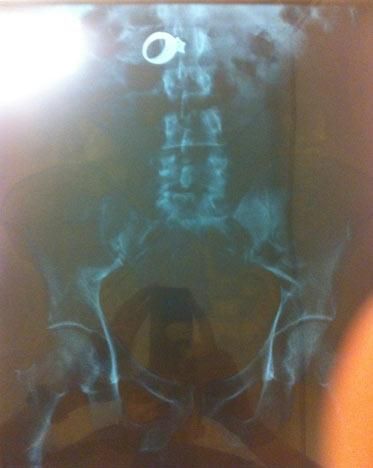

Radiografía de Wilfredo González-Cruz, de 30 años y oriundo de Chicago, quien se tragó un anillo de diamantes tras cometer un robo a una mujer en Cicero, Illionois, el pasado 6 de agosto. El anillo fue recuperado una vez hizo todo el recorrido por su cuerpo, y González, fue arrestado.